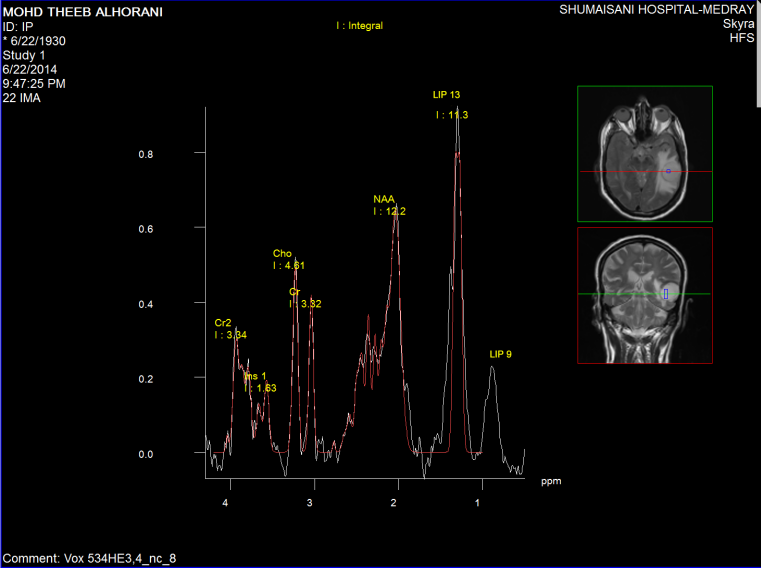

Spectroscopy was done the day before surgery, supporting data for MTS (Figure1-6).

Figure-1: Short TE spectroscopy  inside the mass showing elevated LIP 13 and LIP 09 with slight elevation of Cho and NAA  suggesting the diagnosis of MTS  more than glioblastoma multiforme.